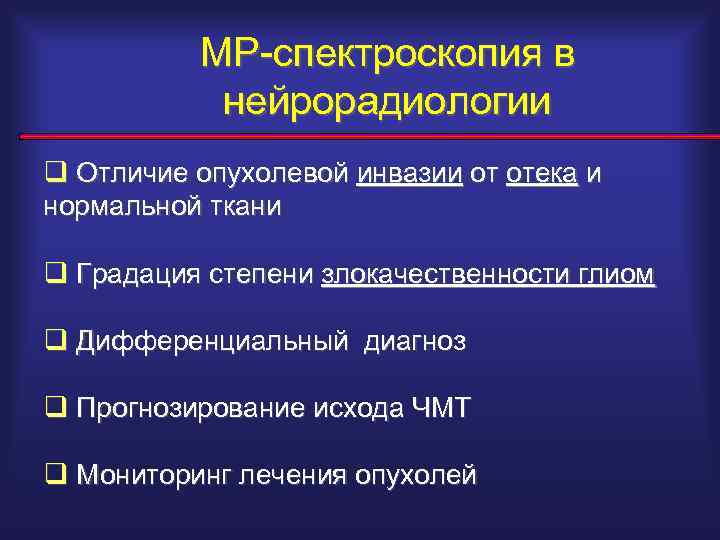

MР-спектроскопия в нейрорадиологии q Отличие опухолевой инвазии от отека и нормальной ткани q Градация степени злокачественности глиом q Дифференциальный диагноз q Прогнозирование исхода ЧМТ q Мониторинг лечения опухолей